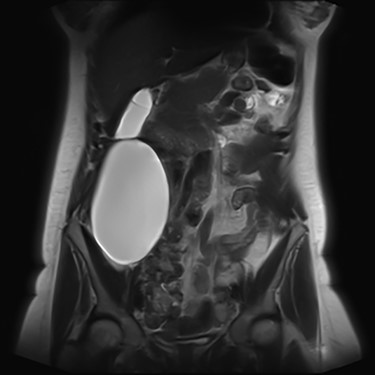

We present an extremely rare and isolated case of primary mixed serous and mucinous cystadenoma in a 49-year-old otherwise fit and healthy female patient. She was referred to our consultant with a history of discomfort on the right side of her abdomen for few years, which increased gradually with no other complains. The patient had further investigations conducted including computed tomography (CT) (Figs 1 and 2) that demonstrated the position and size of the lesion. The magnetic resonance imaging (MRI) revealed a large cystic lesion in the right retroperitoneal region shown in Figs 3 and 4. Her full blood count, inflammatory markers, urea and electrolytes and liver function tests were within the normal limit. Consequently, the patient had a laparoscopic resection of an isolated retroperitoneal cyst. At surgery, the cystic lesion seemed to be arising from mesentery and the lesion was dissected intact and completely excised. Histopathology revealed a benign mixed serous and mucinous cystadenoma as shown in Fig. 5. The patient was discharged from the hospital with no complications and fully recovered on follow-up review. Patient was discussed in a multidisciplinary team meeting and the recommendation was for no further management.